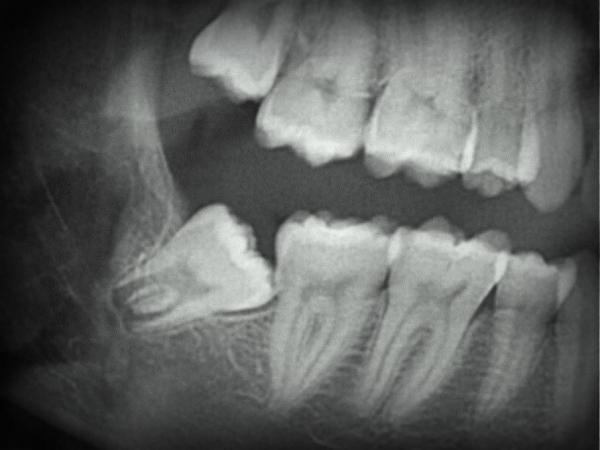

Фото 1. Рентгеновский снимок челюсти, по нему можно определить расположение зуба, что поможет выбрать метод удаления.

- Обязательный рентгенографический снимок. Цель – выявить количество, расположение и степень переплетённости корней, узнать наклон восьмёрки, спланировать последующее удаление и определиться с требуемыми инструментами.

- Ортопантомография – рентгенографический 3D снимок, используется для точного определения строения восьмёрки и выбора метода экстракции.